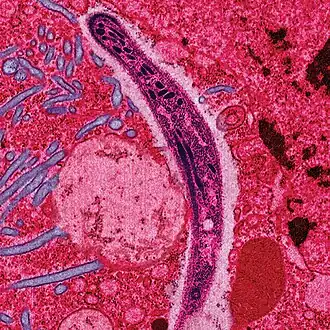

Apicomplexa (do latim apex, ponta ou topo + complex, trançado + a, sufixo) é um grande grupo taxonómico de protozoários, com cerca de 5000 espécies, caracterizados pela presença de um tipo de plastídeo, o apicoplasto, e um complexo apical nos estágios esporozoíto e merozoíto de seu ciclo de vida.[1]

Todos os membros deste filo têm um estágio infeccioso — o esporozoíto — que possui três estruturas distintas no complexo apical. O complexo apical consiste de um conjunto de microtúbulos dispostos em espiral (conoide), uma organela secretora (roptrias), e um ou mais anéis polares. Corpos secretores adicionais, delgados e elétron-densos (micronema) cercados por um ou dois anéis polares podem também estar presentes. É esta estrutura que dá o nome ao filo.

Um outro grupo de organelas esféricas são distribuídos por toda a célula em vez de estar localizada no complexo apical e são conhecidas como grânulos densos. Têm tipicamente um diâmetro médio de cerca de 0,7 micrômetros. A secreção do conteúdo ocorre após a invasão do parasita e posterior localização dentro do vacúolo parasitário, e pode persistir por vários minutos.

- A mitocôndria tem crista tubular.

- A célula é cercada por uma película de três membranas celulares (estrutura alveolar) penetrada por micróporos.